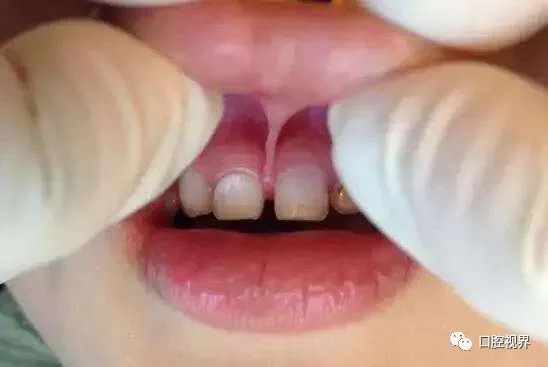

唇系带过低

这个问题多出现在上唇。

由于唇系带退缩不正常,孩子长牙后唇系带的位置仍然很低,就可能使得门牙中间留有一道大缝隙。

换牙期间,家长如果发现孩子的唇系带还是很粗大且水平很低,可千万要格外重视!